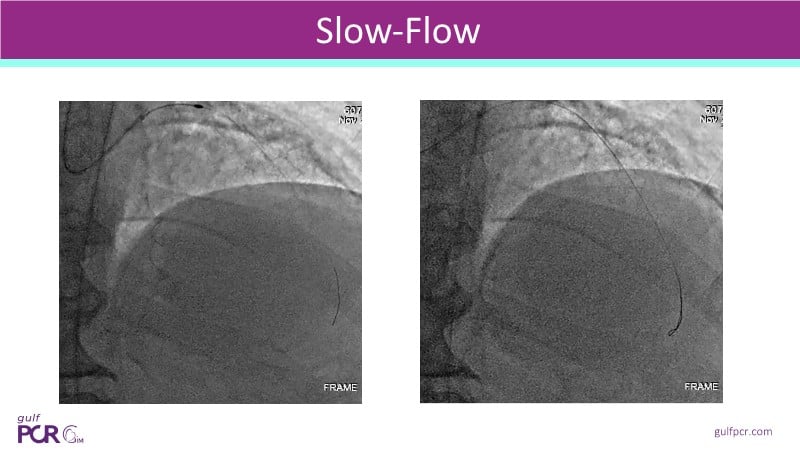

- To identify vulnerable plaques: NIRS detects lipid-rich plaques that are invisible to angiography. This allows interventionalists to anticipate complications like distal embolisation or no-reflow and adjust their approach accordingly